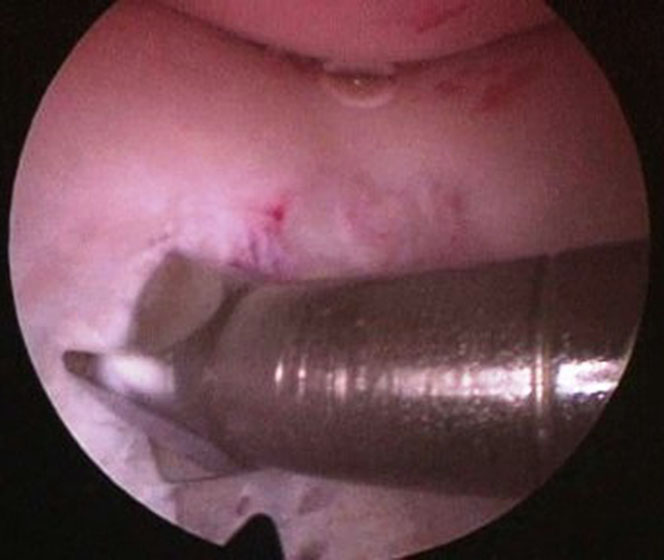

Se procede luego a realizar el portal posterointerno. Dado que no se reseca el remanente HPM, el espacio para acceder a la cápsula posterointerna se encuentra reducido, para ampliarlo realizamos una mínima “notchplastia” en la parte posterior del cóndilo interno (Fig. 4). Con la visión desde el portal anterointerno colocamos un switcher, de los utilizados en cirugía de hombro, desde el portal anterolateral ubicándolo entre el remanente ligamentario y el cóndilo interno (Fig. 5). Luego se pasa la cánula de irrigación guiada por el switcher y se accede con la óptica a la cápsula posterointerna, bajo visión directa colocamos una aguja espinal para localizar el portal, completando con bisturí para luego colocar la cánula de trabajo (Fig. 6). En este punto se vuelve a pasar el artroscopio al portal anterointerno, se introduce el shaver por la cánula del portal posterointerno, y se realiza la limpieza de la capsula posterior, siempre con la hoja de corte hacia anterior para evitar la lesión de estructuras vasculonerviosas. Se continúa alternando los portales anterointerno y posterointerno con visión, shaver, pinza basket y raspas de 90º, hasta completar la desinserción de cápsula posterior e identificar el remanente distal del ligamento sin afectar la inserción. En los casos en que la lesión ha sido en la sustancia colocamos la guía tibial distal a la inserción tibial (Fig. 7). Si la lesión ha comprometido la inserción tibial, levantamos la cicatriz que encontremos y colocamos la guía por debajo del remanente (Fig. 8). Para la introducción de la guía sin lesionar los remanentes ni el LCA se coloca la óptica en el portal anteroexterno y se controla el ingreso de la guía por el espacio entre el remanente y el cóndilo interno (Fig. 9). Se pasa el clavo guía, siempre cuidando de llegar en forma motorizada hasta contactar la cortical posterior y se completa el pasaje golpeando con martillo para evitar una salida brusca del mismo. Se pasa la fresa canulada del diámetro adecuado, protegiendo la emergencia de la misma con una cureta. Una vez completado el túnel tibial, se pasa un alambre o cable desde el orificio externo tibial hacia proximal, con visión en portal posterointerno, al ver emerger el alambre o cable por el orificio tibial posterior, se vuelve la óptica al portal anterointerno para controlar el pasaje de un grasper desde anteroexterno a través del intervalo entre HAL y LCA, y dirigirlo hacia posterior (Fig. 10); se vuelve con la óptica al portal posterointerno y se visualiza la recuperación del alambre o cable con el grasper hacia la parte anterior de la rodilla (Fig. 11). Se amplía el portal anteroexterno y se anuda la sutura tractora del injerto al alambre o cable, y traccionando desde el orificio distal del túnel tibial se hace ingresar el injerto en forma retrógrada a la articulación y, luego, al túnel tibial por su orificio posterior. En caso que se utilice el injerto de tendón cuadricipital la parte tendinosa irá al túnel tibial y el bloque óseo al femoral. Una vez ingresado el injerto al túnel tibial, se vuelve la óptica al portal anterointerno, en el portal anteroexterno tendremos la sutura tractora del extremo “femoral del injerto”, es aconsejable en este punto llevar el injerto lo más distal posible para tener mejor visión articular, enhebrar la sutura tractora en una cánula de unos 6 mm de diámetro, para asegurarse que la sutura tractora y la clavija pasasutura pasan por el mismo espacio sin incluir tejido sinovial o grasa retrorrotuliana (Fig. 12). Se procede a pasar la aguja pasasutura por el túnel femoral, saliendo por las partes blandas de la parte medial de la rodilla, se tracciona y se asciende el injerto colocándolo en el túnel femoral. En caso que el injerto tenga bloque óseo puede ser necesario redirigir el mismo para ubicarlo en el túnel femoral, para esto ubicamos la visión en el portal anteroexterno y por el portal anterointerno utilizamos el trocar romo o el palpador para realizar una polea y mejorar la tracción para que ingrese el taco óseo en el túnel femoral (Fig. 13). Luego se realiza la fijación femoral con tornillo de interferencia de titanio o biodegradable. A continuación liberamos el manguito neumático, porque creemos que produce un espasmo en los isquiotibiales que dificulta la reducción de la tibia, dejamos pasar unos minutos que utilizamos para colocar un tornillo maleolar con arandela, distal al orificio externo del túnel tibial para realizar una segunda fijación de la parte tibial. Preferimos hacerlo antes de colocar el tornillo interferencial, porque esto generará una presión hacia posterior de la tibia. Se realiza la reducción tibial en 90° de flexión de la rodilla, se tracciona del injerto y se coloca el tornillo de interferencia tibial, luego la sutura remanente (polyester 5) se anuda en el tornillo maleolar completando la 2da fijación. Por último se constata con una nueva visión articular la posición y tensión del injerto (Fig. 14).

Figura 4